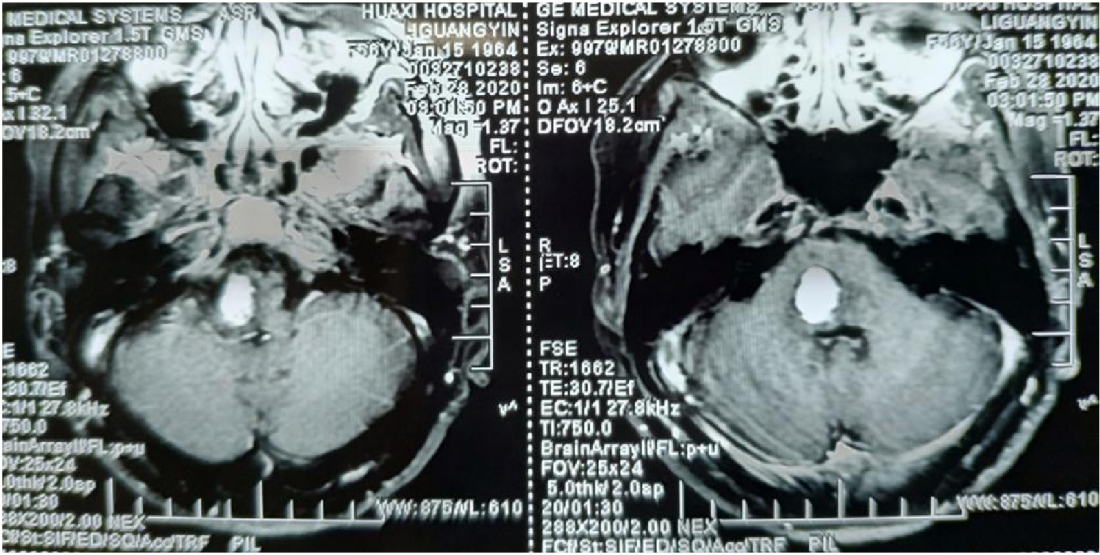

患者李某银,女,56岁。因“头晕,口角歪斜伴左侧肢体麻木乏力2月”入院,以无明显诱因头晕伴左侧面部口角歪斜,并左侧肢体麻木乏力为主要表现,于外院行脑MR增强提示脑干占位性病变,血管母细胞瘤可能性大。

MR显示桥脑右侧高信号影,肿瘤位于四脑室界沟上方之桥脑部分,邻近面丘及动眼神经核,因此患者出现面瘫。

肿瘤位于桥脑与延髓交界处

面神经丘受压明显